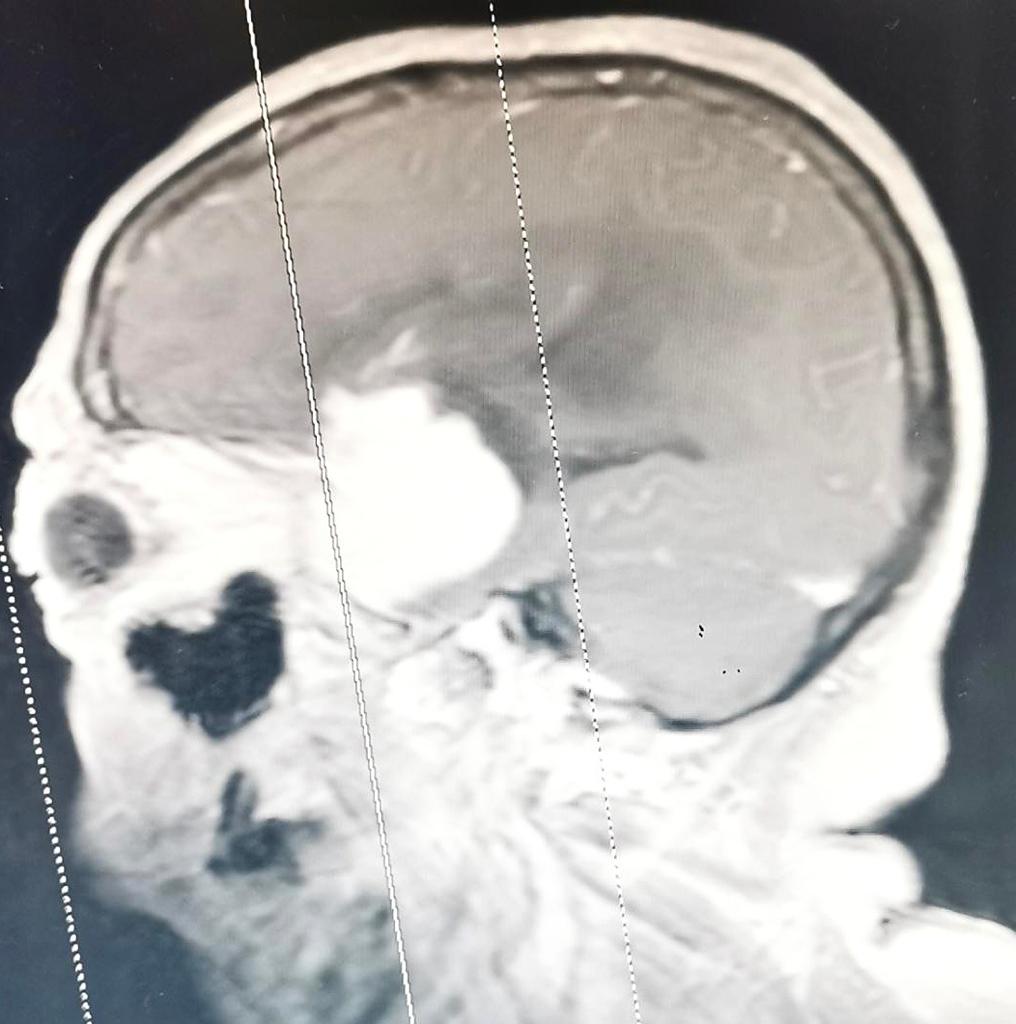

I don’t unpack and live here, but as I’m sure you all know - it’s always in the back of my mind.

#chronicillness#MultipleSclerosis#meningioma pic.twitter.com/51YFpypSNG